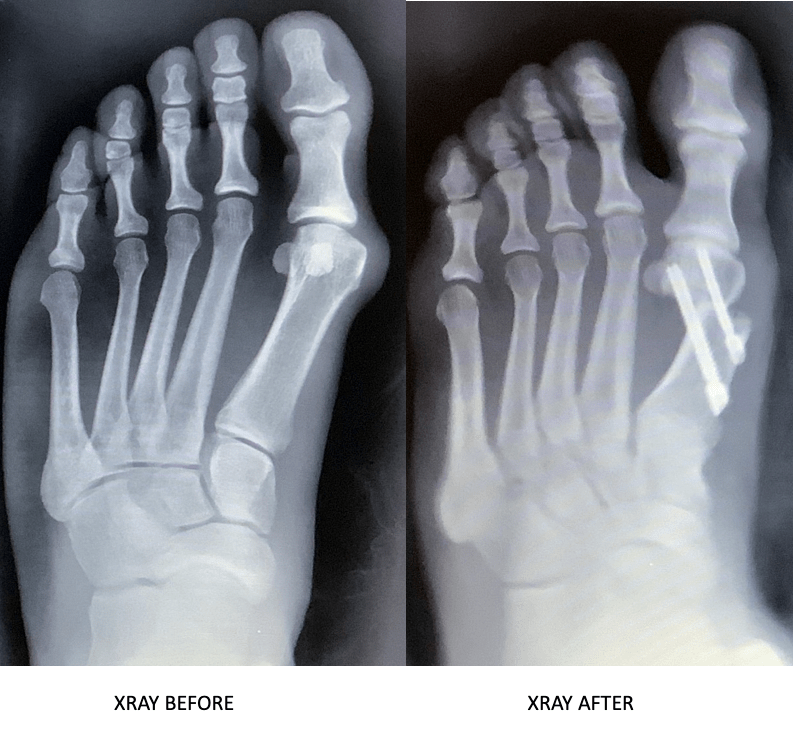

Total ankle replacement before & after The Orthopaedic Group, P.C. Why Elevate Ankle After Surgery Lying down for an hour in the late morning or afternoon helps reduce swelling. Wounds usually seal and stop bleeding three days after operating. How long should i keep my foot elevated after surgery? They will guide you on the optimal duration and frequency of foot elevation based on your case and the type of surgery you underwent. Ankle surgery. Why Elevate Ankle After Surgery.